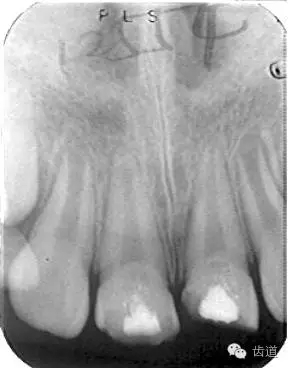

術(shù)后

術(shù)前

術(shù)后199日

術(shù)后1084日